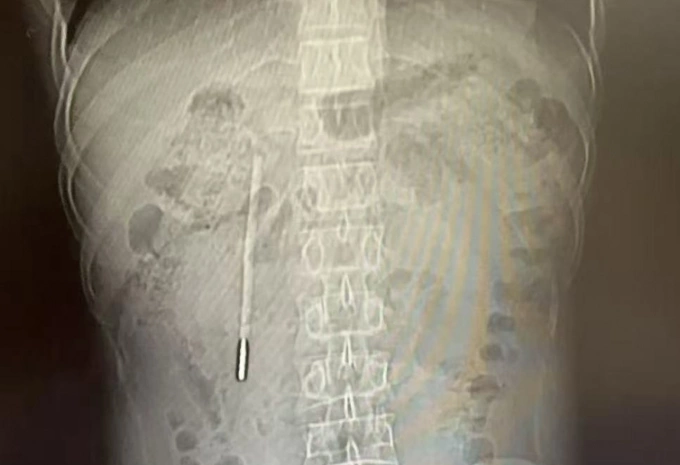

Truyền thông Trung Quốc đưa tin Wang đi khám do có triệu chứng đầy bụng, khó tiêu kéo dài. Kết quả chụp CT ổ bụng phát hiện một dị vật nằm ở tá tràng, được xác định là một chiếc nhiệt kế thủy ngân. Đầu nhọn của nhiệt kế đã tì sát vào thành ruột, có thể gây thủng ruột hoặc xuất huyết ồ ạt bất cứ lúc nào.

Phim chụp cho thấy một chiếc nhiệt kế thủy ngân trong bụng bệnh nhân. Ảnh: Wenzhou Metropolitan Daily